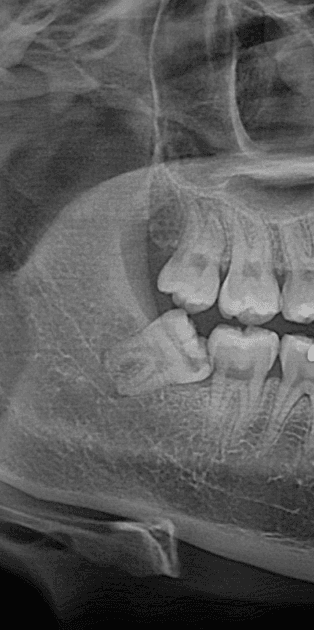

사랑니 4개, 하루에 다 뽑아도 될까요? - 이미지 1

사랑니 4개, 하루에 다 뽑아도 될까요? - 이미지 2

사랑니 4개, 하루에 다 뽑아도 될까요? - 이미지 3

사랑니 4개, 하루에 다 뽑아도 될까요? - 이미지 4

사랑니 4개, 하루에 다 뽑아도 될까요? - 이미지 5